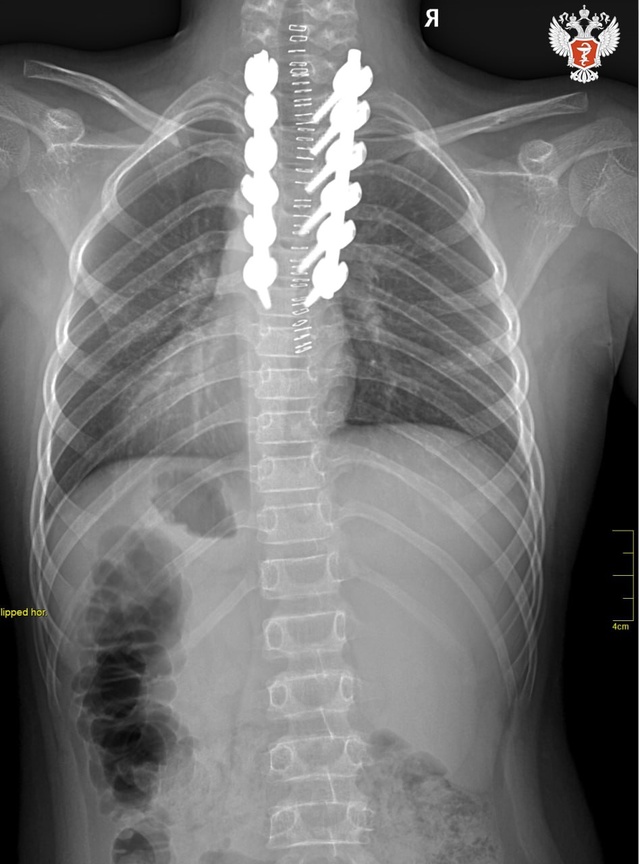

📋 Врачи стабилизировали позвонки при помощи специальной металлической конструкции. В будущем, когда имплантат выполнит свои функции, врачи удалят его.